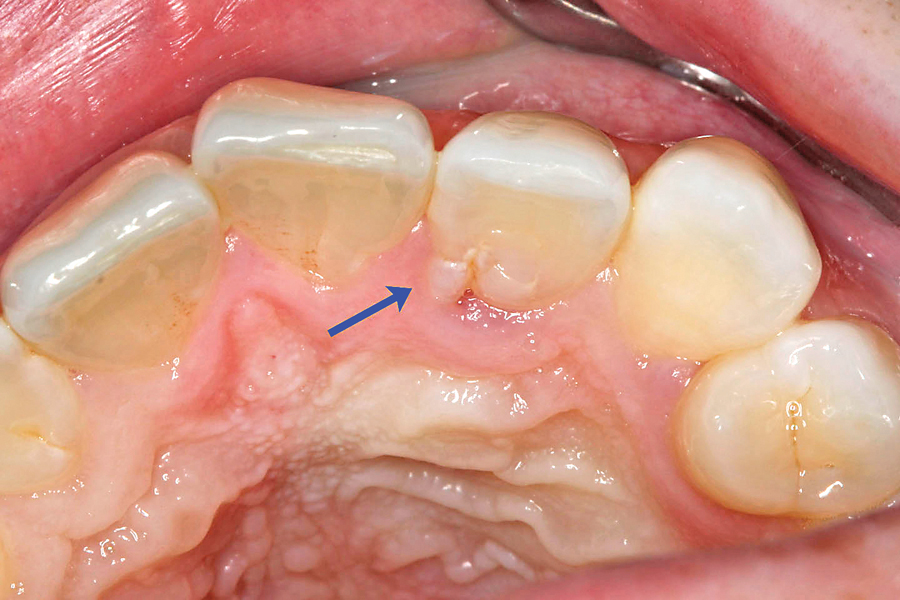

Bilateral dens evaginatus (talon cusp) in permanent maxillary lateral Extra Cusp On Front Tooth It was first described by mitchell in 1892. Extra buccal cusp on a mandibular molar. Talon cusp is a rare dental abnormality where an extra cusp develops on the inner side of the upper incisors starting from the neck of the tooth. Put simply, the cusp of carabelli is just an extra bump on one or two of your teeth.. Extra Cusp On Front Tooth.

Mandibular talon cusp a rare dental anomaly BMJ Case Reports Extra Cusp On Front Tooth Put simply, the cusp of carabelli is just an extra bump on one or two of your teeth. 10 this extra cusp occurs on the. It was first described by mitchell in 1892. According to the journal of clinical and diagnostic research, these possibly form from. Two extra cusps (or two fused paramolars) on the buccal surface of a maxillary. Extra Cusp On Front Tooth.